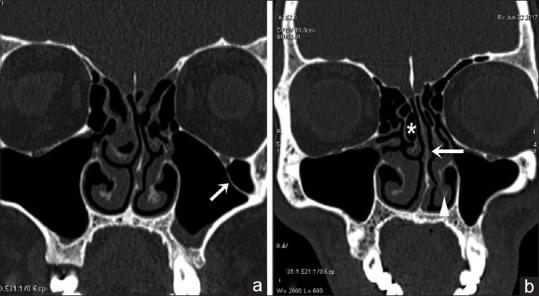

Among 250 study population, 100 were females and 150 males. Among these 423 cases of anatomical variants were observed. The most common anatomical variants were pneumatization of the middle nasal turbinates 30.73%. This is followed by agger nasi cells 21.64%, Haller's cells 22.91%, septal deviation 21.91%, and sphenoid sinus septation (20.18%).

CT is the gold standard in the radiologic investigation of the paranasal sinuses, sinonasal lesions, and inflammatory disease or pre- and post-surgical assessment. It has the capability of disclosing in greatest detail any anatomical variations, which could be causing or precipitating the sinusitis.